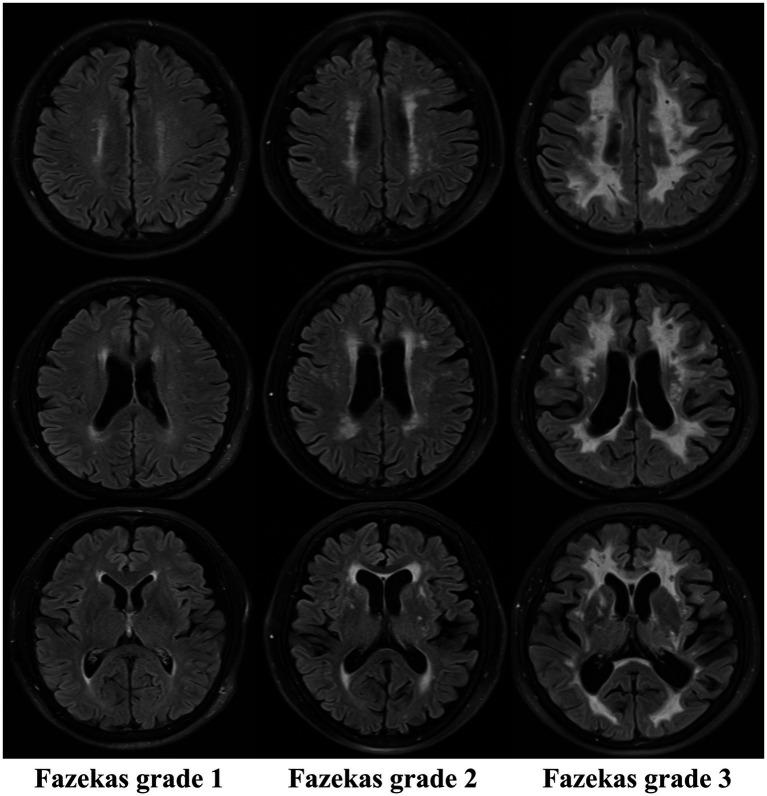

White matter hyperintensity (WMH) is the core imaging hallmark of cerebral small vessel disease (CSVD). This phenomenon is closely related to nervous system damage, such as cognitive impairment, dementia and increased risk of stroke. However, traditional diagnostic methods have significant limitations in terms of quantitative assessment, analysis of pathological mechanisms, and clinical decision support, which severely restrict their clinical application. Through high-throughput feature extraction and comprehensive analysis of clinical, laboratory, histological, and genomic data, radiomics in its current form can not only achieve the high-precision identification and staging of WMH but also help to reveal its pathological mechanism, which has shown important value in the diagnosis, prognosis, and evaluation of WMH-related diseases. Against this backdrop, we strictly adhered to the norms of systematic literature reviews, conducting a comprehensive and transparent literature search. We also thoroughly reviewed the data using a predefined strategy and strict inclusion/exclusion criteria (detailed in the text). This article systematically reviews the progress of radiomics research in characterizing the pathological mechanism of WMH and in the early identification, classification and prognostic evaluation of related diseases, aiming to provide a theoretical basis and a technical reference for the early identification of high-risk groups, the optimization of diagnosis and treatment decision-making, and the practice of collaborative patient management.